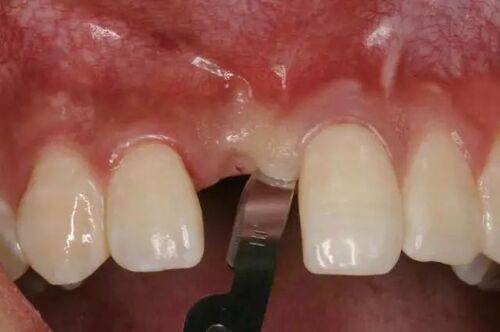

图2:冠状面看位于囊肿上方和颊侧(一般偏舌侧)

下牙槽神经被提起后,骨板上的凹槽显露出来。进一步对CT图像进行检查,确认下颌神经从颊侧骨板穿出,并且在神经与囊肿之间存在正常骨质,下颌神经在一个开放的通道内自由移动。

关于下牙槽神经的走向,已有众多解剖学和影像学研究。在大多数情况下,下颌神经位于阻生第三磨牙下方,且其与牙齿的位置关系通常在颊舌方向上变化。Maegawa等人发现,74%的下颌神经在下颌第三磨牙下方和舌侧运行。本案例中,下颌神经在第三磨牙上方和颊侧的位置非常罕见。我们认为这是第一个临床与放射学关联的外露下颌神经报告(图2、图3)。目前文献中尚无相关变异发生率的信息。

有观点认为我们的发现可能是囊肿造成的,而非解剖变异。然而,考虑到没有骨扩张或下颌轮廓变化,我们认为这种变异更可能是解剖性的。囊肿与神经之间存在完整的骨板进一步支持了这一假设。虽然已知牙源性囊肿可导致下颌神经管位移,但在18.1%的牙源性囊肿中,下颌神经的外露未被报告。因此,我们认为在此情况下看到的神经外露更可能是解剖变异,而非病理性结果。